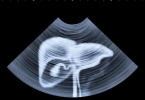

• 超声波能否检测出脂肪肝

超声波能否检测出脂肪肝

超声波一般能检测出脂肪肝,是诊断脂肪肝的常用影像学检查方法之一。超声波检查通过高频声波反射成像,能够清晰显示肝脏形态、大小及回声特征。脂肪肝患者的肝细胞内有过多脂肪沉积,会导致肝脏回声增强、远场衰减等 ...

• 列举酒精性脂肪肝的检查手段

列举酒精性脂肪肝的检查手段

酒精性脂肪肝的检查手段主要有肝功能检查、影像学检查、肝脏弹性检测、肝活检、血液生化检查等。1、肝功能检查肝功能检查是诊断酒精性脂肪肝的基础手段,通过检测血清中的谷丙转氨酶、谷草转氨酶、γ-谷氨酰转移酶等 ...